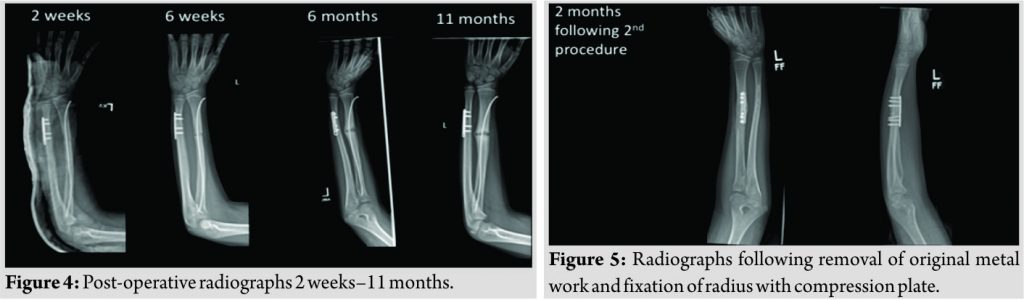

He was seen routinely at 2 weeks, 6 weeks, and 6 months, where radiographs confirmed healing of the ulnar fracture, but not of the radius (Fig. 4). At 11-month post-initial surgery, a computed tomography scan was performed which confirmed non-union at the radial fracture site. The decision was then made to explore the fracture non-union site. At this stage, the initial metalwork was removed, and the radial fracture site was fixed with a compression plate. Samples taken intraoperatively ruled out any infection or bone pathology. At 2-month post-second surgery, there was a fracture union of the radial site (Fig. 5).